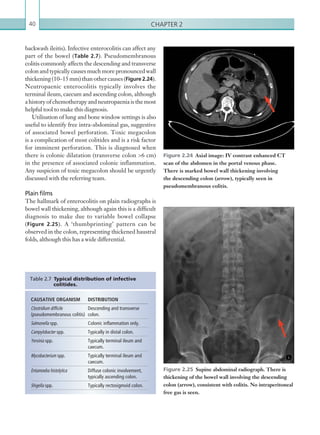

the abdomen in the delayed phase. On delayed imaging,

further contrast has accumulated within the lumen

of the ascending colon as a result of continued, active

haemorrhage at this site.

serpiginous enhancing vessels in the region of the distal

oesophagus. Findings suggestive of liver cirrhosis

and portal hypertension, such as an irregular liver

outline and splenic enlargement, should prompt

the search for oesophageal varices (Table 2.4;

Figures 2.9, 2.10).